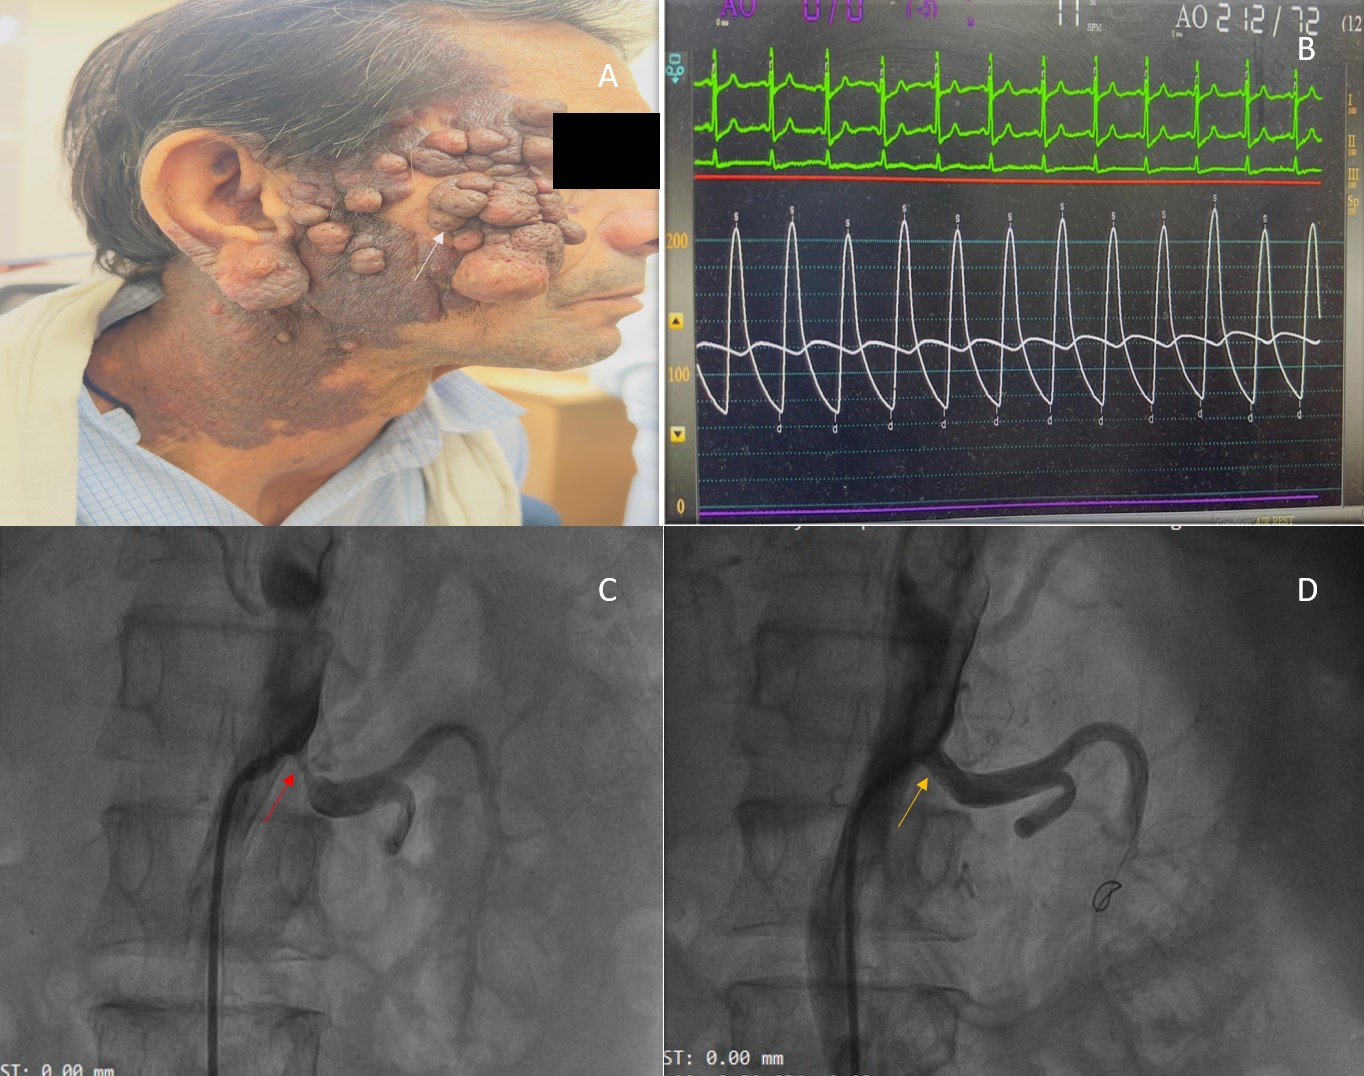

On examination, his BP was 220/100 mm Hg and his heart rate was 90 beats per minute. Multiple cutaneous neurofibromas and areas of hyperpigmentation were noted over his face and neck (Figure A). Electrocardiography demonstrated normal sinus rhythm with evidence of left ventricular hypertrophy. Transthoracic echocardiography revealed concentric left ventricular hypertrophy with preserved systolic function, without evidence of aortic coarctation or stenosis. Laboratory investigations showed elevated serum creatinine (1.7 mg/dL; normal 0.6-1.1 mg/dL).

In the catheterization laboratory, the patient’s invasive BP measured 212/72 mm Hg (Figure B). The right renal artery had a mild plaque at the ostium and was free of significant disease. Left renal angiography demonstrated 90% proximal stenosis of the left renal artery (Figure C). The lesion was crossed with a Whisper wire (Abbott), followed by predilatation using a 4 ×18-mm Apollo balloon (BrosMed Medical). A 7×18-mm Herculink Elite stent (Abbott) was then deployed. Postdilatation with a noncompliant balloon and ostial flaring were performed, resulting in a well-expanded stent with satisfactory distal flow (Figure D).